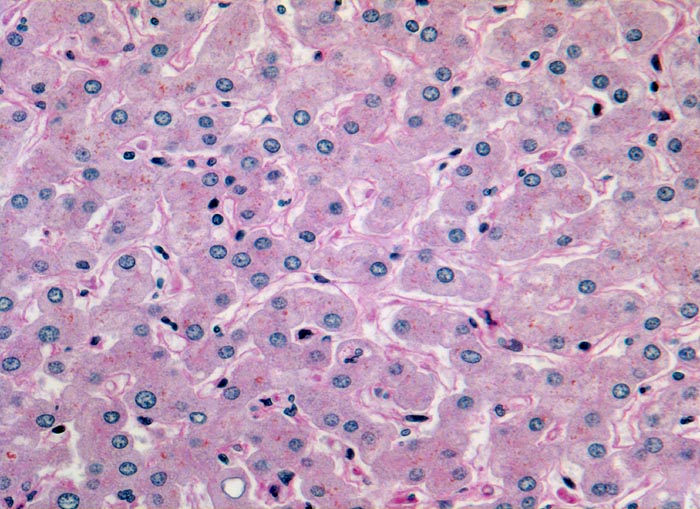

Das histologische Bild der akuten Hepatitis vom Virustyp ist gekennzeichnet durch eine lobuläre Entzündung bei fehlender portaler Fibrose und nur geringer entzündlicher Infiltration der Portalfelder. Es finden sich ballonierte Hepatozyten, Apoptosen (> 1164) und fleckige Nekrosen. Perivenuläre Nekrosen, Brückennekrosen oder konfluierende multilobuläre Nekrosen und eine läppchenzentrale Cholestase können vor allem in klinisch fulminant verlaufenden Fällen nachgewiesen werden. Zahlreiche Makrophagen, welche Diastase-PAS positives Zeroidpigment (> 4319) von phagozytierten nekrotischen Hepatozyten enthalten, zeugen im subakuten Stadium von einer abgelaufenen akuten Hepatitis mit Parenchymnekrosen. Eine Unterscheidung der verschiedenen Typen der viralen Hepatitis und einiger Formen medikamentöser Hepatitiden gelingt rein morphologisch aufgrund des unspezifischen Bildes meist nicht. Für eine ätiologische Klassifizierung sind zusätzliche klinische Angaben erforderlich (Anamnese, Medikamente, Serologie).

Morphologische Merkmale:

• Regelrechte Läppchenarchitektur.

• Lobuläre gemischte Entzündung.

• Apoptosen (hypereosinophile abgerundete Leberzellen).

• Portale gemischte Entzündung.

• Fehlende Fibrose.